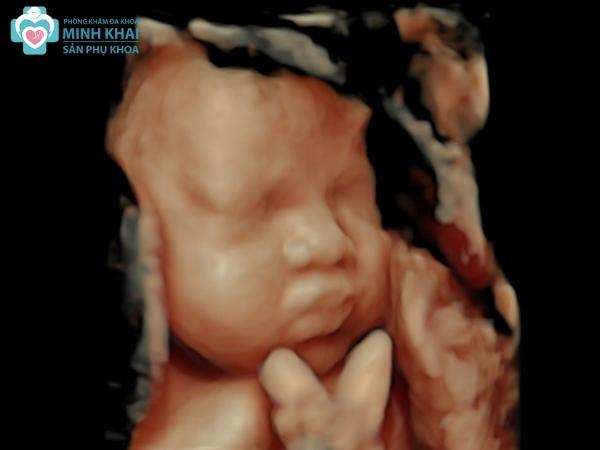

Chúng cho phép thu lại những hình ảnh, đoạn phim ngắn bên trong cơ thể một cách chân thực. Các thông số, tình trạng của thai nhi cũng được xác định khá rõ ràng thông qua cách khám thai này. Từ đó bác sĩ có thể chẩn đoán được những đặc điểm của bào thai về hình thái, kích thước, số tuổi,... cũng như phát hiện các dị tật bẩm sinh.